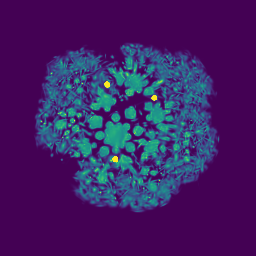

Synthetic Scenes